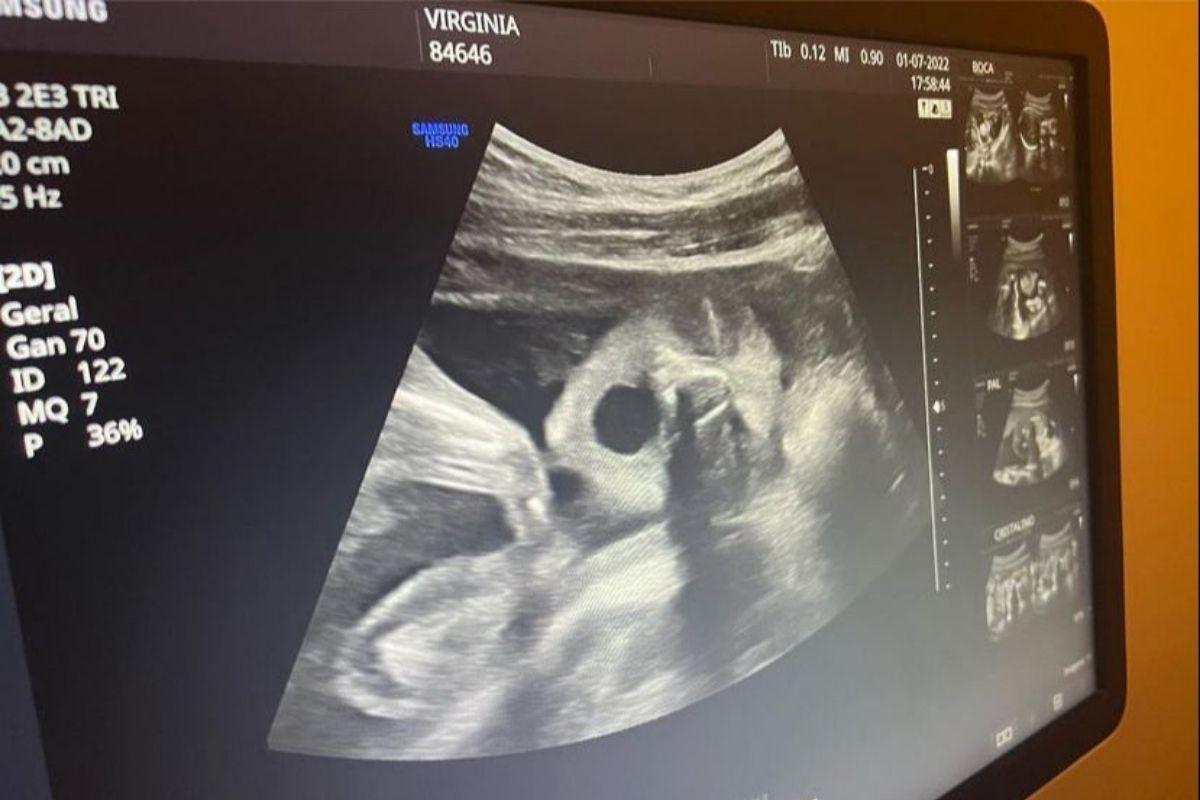

Ao realizar a ultrassonografia, na qual era possível ver os olhos e a boca da filha, Virginia acabou percebendo a menina de seis meses bocejando dentro de sua barriga. A influenciadora não perdeu tempo e registrou o lindo momento nas suas redes: “Oi, galera, Florzinha aqui! Mamãe e papai foram me ver e eu mostrei minha boquinha e bocejei 2x no ultrassom. Trabalhando muito por cá, soninho mix. 6 meses”, contou Virginia na legenda das duas fotos tiradas durante o exame.